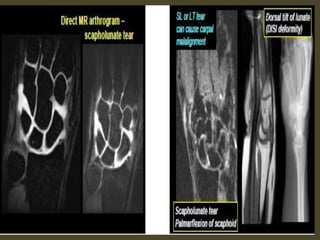

Scapholunate dissociation. Note the widened scapholunate space (“Terry Thomas”

sign) and the foreshortened scaphoid with a “scaphoid ring” sign (arrows).

Adjacent is British comedian Terry Thomas and his famous teeth.

Scapholunate ligament rupture.

Scapho - lunate ligament tear

Scapholunate and lunotriquetral ligament tear.

1. Scapholunate ligament tear, dorsal angulation of the lunate and

proximal migration of the capitate consistent with a DISI deformity.

2. Tear of the lunotriquetral and triscaphe ligaments.